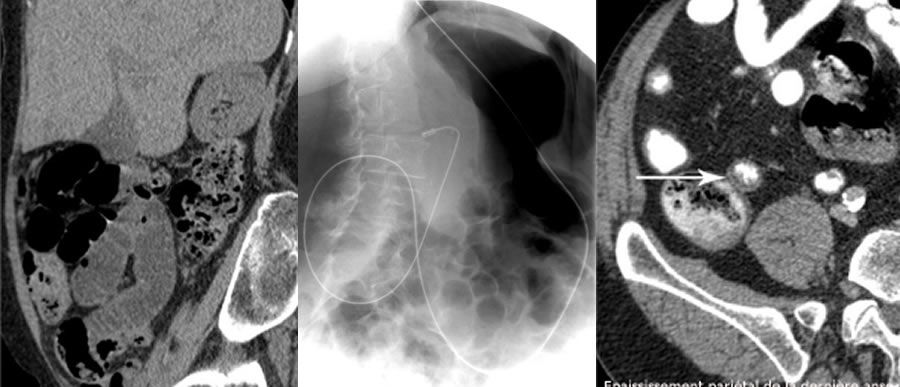

L’entéroscanner est actuellement l’un des examens les plus performants pour l’étude des différentes anomalies de sa paroi.

Les principales indications de l’entéroscanner sont l’exploration d’hémorragie digestive sans cause évidente retrouvée, la recherche de lésions de la paroi de l’intestin grêle et le bilan topographique de maladie inflammatoire chronique de l’intestin.

Une sonde naso-jéjunale souple est introduite par une narine après anesthésie locale puis mise en place sous guidage radioscopique jusqu’à l'origine des premières anses de l’intestin grêle.

Dans un second temps, dans la salle du scanner, 2 litres d’eau sont injectés par la sonde, afin de remplir l’ensemble de l’intestin grêle.

L'aquisition des images au scanner intéresse ensuite l'abdomen et le pelvis après injection de produit de contraste par voie intra-veineuse et d’un anti-spasmodique.